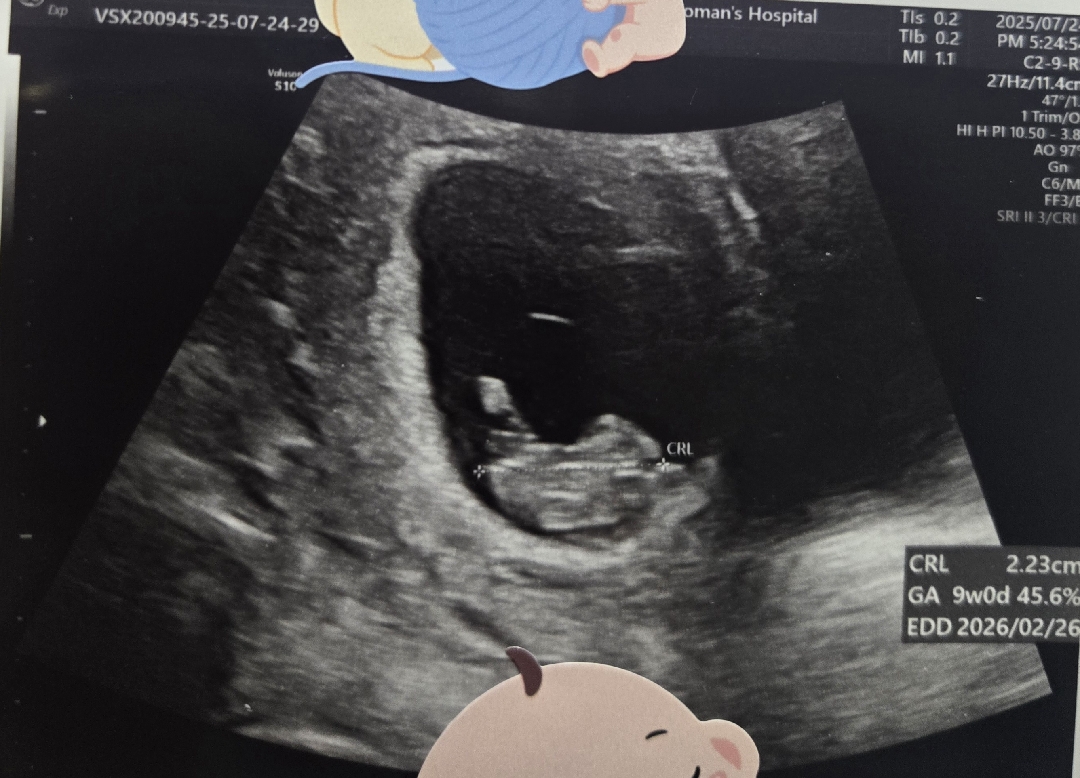

9주5일차예용 지난번 산부인과 다녀왔을때 제가 쉬야를 안하고 봐서 그런지 뿌옇다고...그래서 젤리곰도 못봤는데ㅠㅠ 저는 아무리봐도 어디가 머리고 어디가 다리인지 쌤께서 말씀해주셔도 모르겠더라구용ㅋㅋ 갑 성별이 너무 궁금해져서 여쭤봅니당ㅎㅎ 심장소리는 기차소리같기도하고 말발굽같기도하고 듣는사람마다 다 다르네용ㅋㅋㅠㅠ